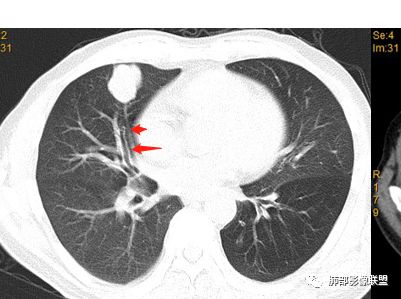

南边:

如果这时候我建议补充下面的层面,最好薄层

看起来堵了

按这个就是堵了

我们一般是找肺动脉,伴行支气管

堵了大方向不支持良性肿瘤

2.近肺门侧隐约见支气管截止。